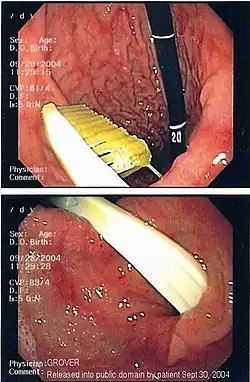

Endoscopic still of gastric foreign body (toothbrush)

Commonly swallowed objects include coins, buttons, batteries, and small bones (such as fish bones),[1] but can include more complex objects, such as eyeglasses,[5] spoons,[6] and toothbrushes[5] (see image).